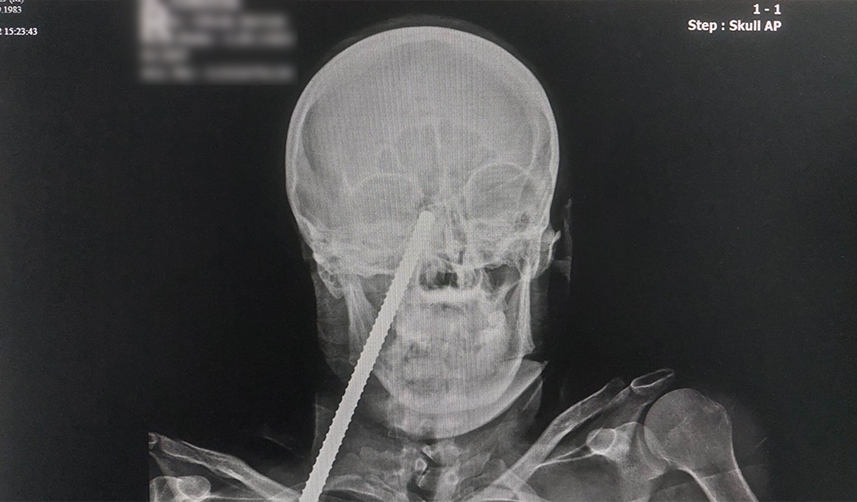

Giresun'da inşaattan düşen işçinin yüzüne demir saplandı

Giresun'da çalıştığı inşaatta düşerek yüzüne demir saplanan işçinin sevk edildiği Samsun'daki hastanede ameliyatla yüzündeki demir çıkartıldı.

Edinilen bilgiye göre, Giresun'da çalıştığı inşaatta demirin üzerine düşen C.S.'nin (39) yüzüne inşaat demiri saplandı. Yüzünde demir saplı halde Giresun'daki hastaneye kaldırılan C.S., ilk müdahalesinin ardından demirin yüzünden çıkartılması için Samsun'a sevk edildi.

C.S., Samsun Eğitim ve Araştırma Hastanesinde ameliyata alındı. Yüzündeki demir çıkartılan Sayar, daha sonra hastanenin yoğun bakım servisinde tedavi altına alındı.